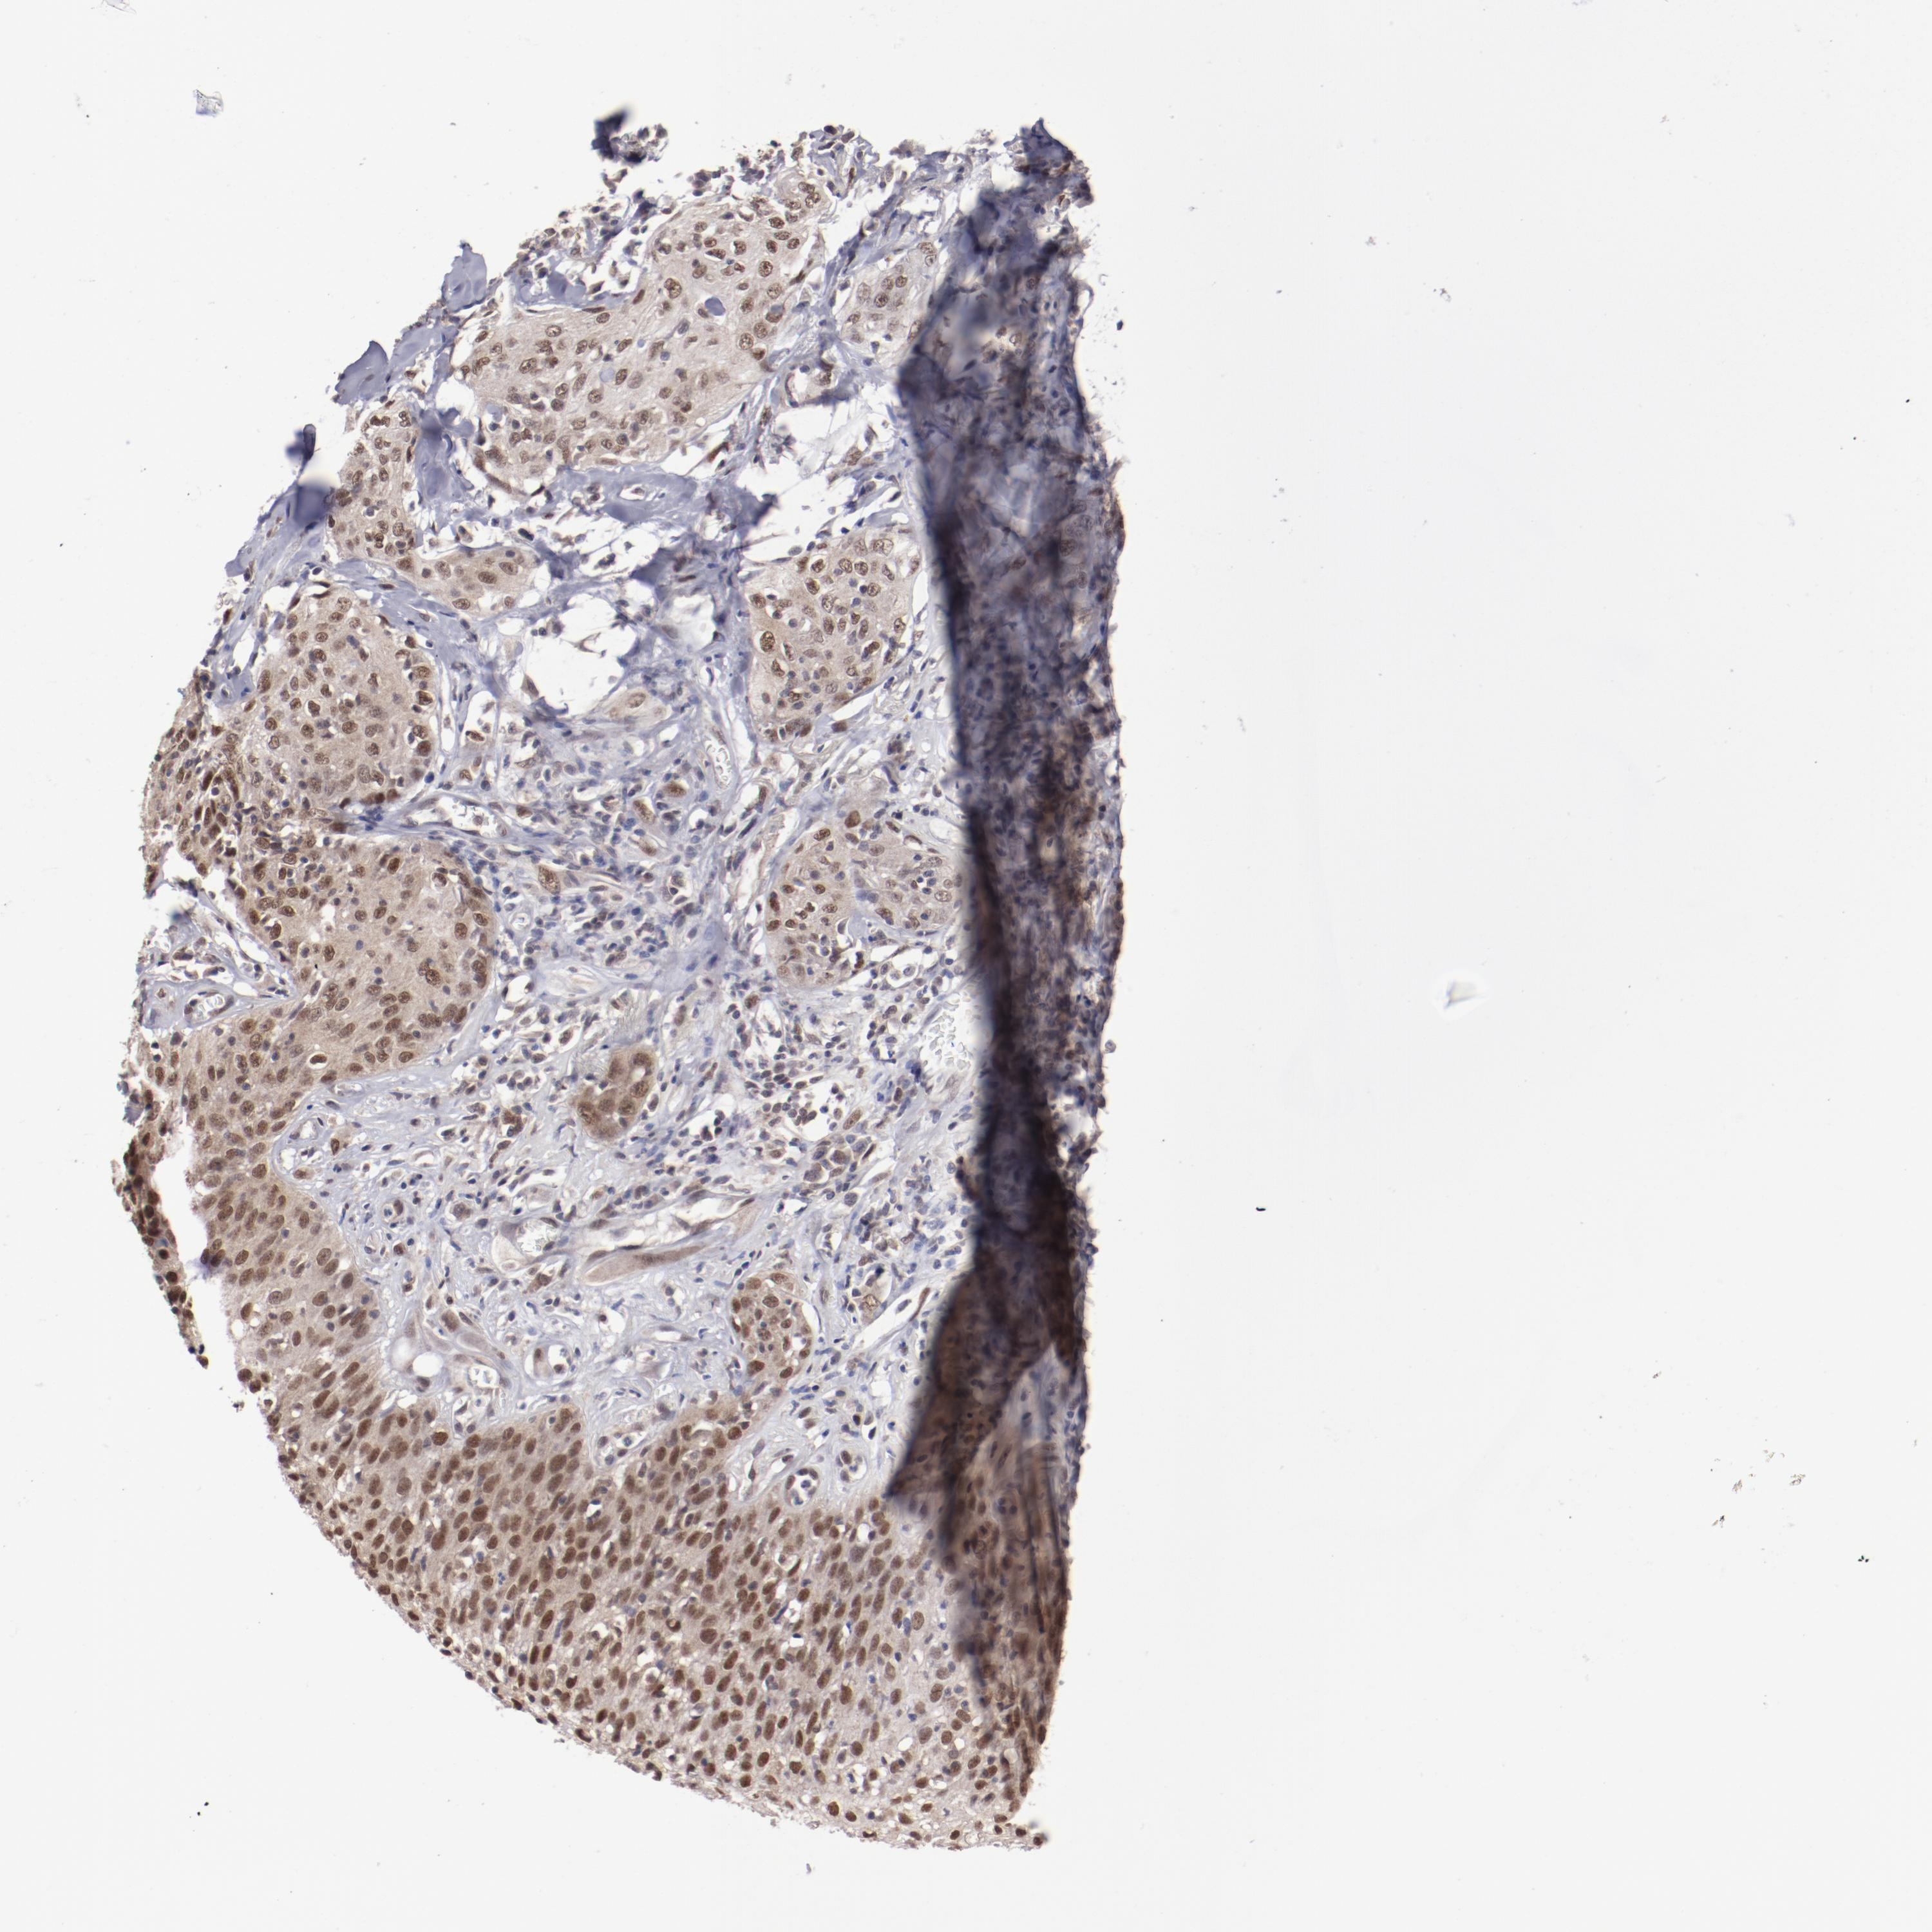

CANCER SKIN CANCER Show tissue menu

Basal cell and squamous cell cancer

SKIN CANCER - Protein expressioni

A mouse-over function shows sample information and annotation data. Click on an image to view it in a full screen mode. Samples can be filtered based on level of antibody staining by selecting one or several of the following categories: high, medium, low and not detected. The assay and annotation is described here.

Each image is clickable and will lead to virtual microscopy that enables deeper exploration of all samples and also displays staining intensity scores, fraction scores and subcellular localization as well as patient and tissue information for each sample.

Antibody HPA001759

Squamous cell carcinoma, NOS

Basal cell carcinoma